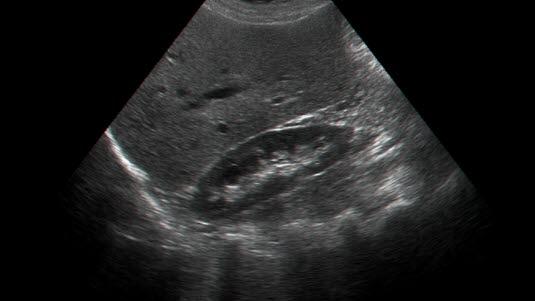

Ultralyd av nyrer og urinveier

Ultralyd fremstiller nyrer, nyrebekken, urinblære og ev. urinledere. Ultralyd gir også gode bilder av pungen/ testiklene ved behov for å undersøke disse organene. Undersøkelsen gir først og fremst informasjon om organenes utseende, mens informasjon om hvordan organene fungerer, er begrenset. Ultralyd kan gjøres uten å ta hensyn til nyrefunksjonen da kontrastvesken bruk ved denne undersøkelsen ikke påvirker disse, dvs. undersøkelsen kan gjøres også ved alvorlig nyresvikt. Fedme gir dårligere bilder. Luft i tarmen gjør det vanskeligere å tyde bildene.

Normale funn viser jevne konturer av nyrene. Normal nyrelengde hos en voksen er 9-12 cm. Normale urinledere lar seg vanligvis ikke fremstille med ultralyd. Urinblæren fremstår i fylt tilstand med en skarp avgrensning.

Ultralyd kan vise nyrestørrelsen, bredden på nyrevevet og kan avklare om det foreligger hydronefrose (utvidet samlesystem). Dersom dette er et medfødt avvik egner ultralyd seg godt til å følge utviklingen av dette.